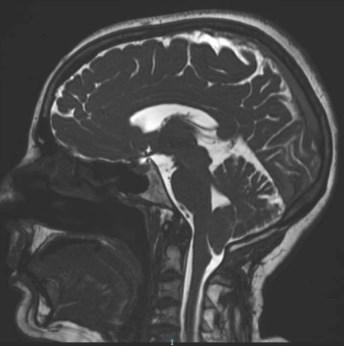

Imagen de resonancia magnética (IRM). Es la primera prueba de diagnóstico debido a que produce imágenes tridimensionales. Ofrece una vista precisa del cerebelo, la médula espinal y el cerebro, con esta prueba se puede definir el alcance de las malformaciones e incluso distinguir la progresión.

Es la que ocurre durante el desarrollo fetal. Se caracteriza por el desplazamiento hacia debajo de las amígdalas cerebelosas hacia el canal espinal cervical, por aproximadamente, cuatro milímetros. Debido a este desplazamiento se bloquean la circulación normal de líquido cefalorraquídeo (LCR) entre el canal espinal y el espacio intracraneal.

En una situación normal, el cerebelo y parte del tallo cerebral se posan en un espacio ubicado por encima del orificio llamado foramen magno. Cuando se presenta la malformación, el cerebelo se ubica por debajo del foramen magno aumentando la presión sobre los nervios y tejidos en la zona.